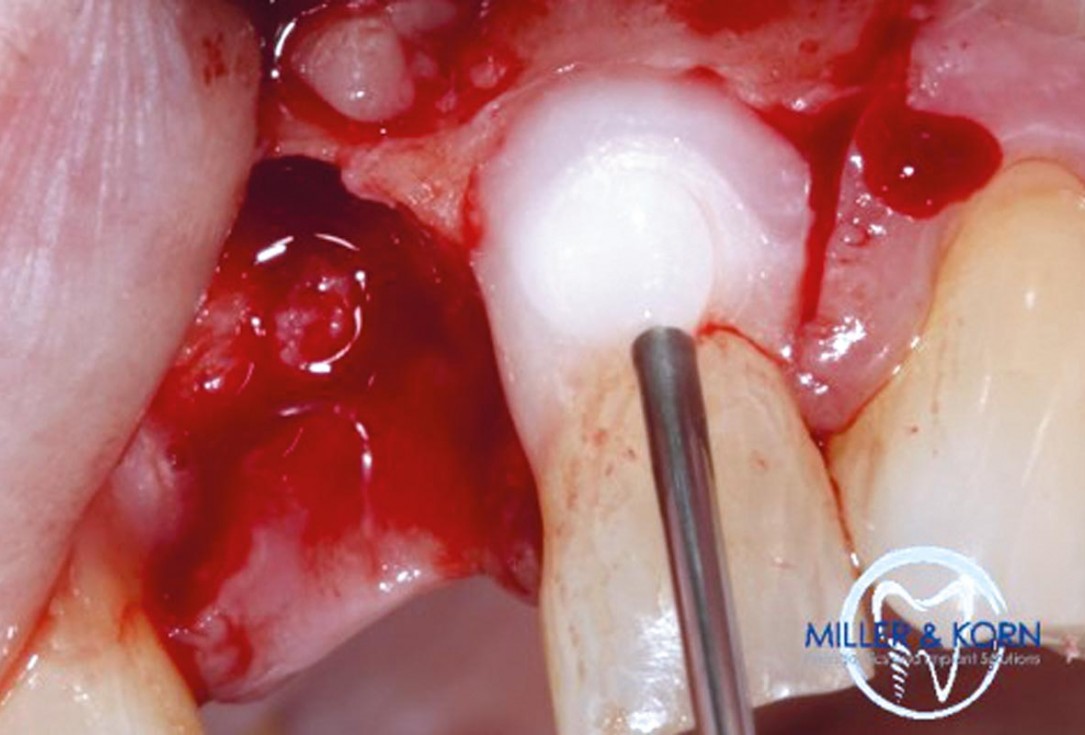

09/39 - Determination of the implant position using a needle drillImmediate implant placement and correction of horizontal and vertical bone loss using an allograft bone ring, cerabone® and Jason® membrane - Drs. Miller and Korn